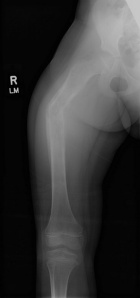

Patient is a 6 y/o female who presented w/ R. thigh pain and inability to bear wt. after attempting to stand for seated position

She c/o R. knee pain for several months w/ fevers and increased inflammatory markers w/ presumed dx. of JRA; PMH: unremarkable

PE: R. thigh swollen/warm with TTP; NVI